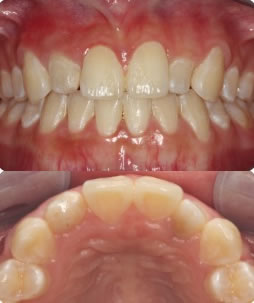

Figure 3: Facial image of maximum intercuspal position Figure 4: Maxillary Occlusal Image